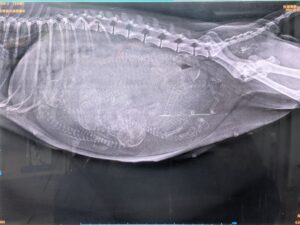

夕方、レントゲン検査撮影 2月1日

頭が5つ!!

降りてきてるようです。

みんな逆子です✧◝(⁰▿⁰)◜✧

産道も通れそうです。